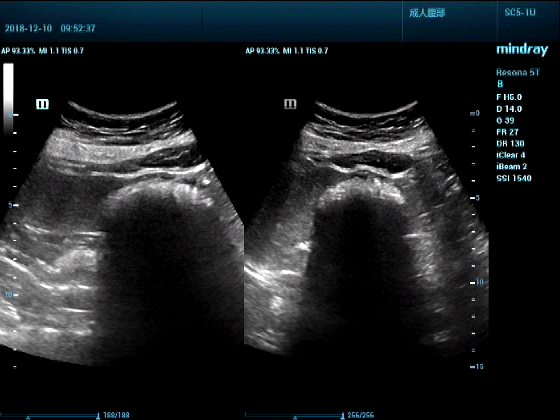

病例一:女,53岁,胃部不适一周来诊

超声可见:胃腔内见一小鸡蛋大强回声团块,后方伴强声影,位置活动。

问及病史吃山楂,柿子。

超声提示:结合临床考虑胃结石,治疗后复查